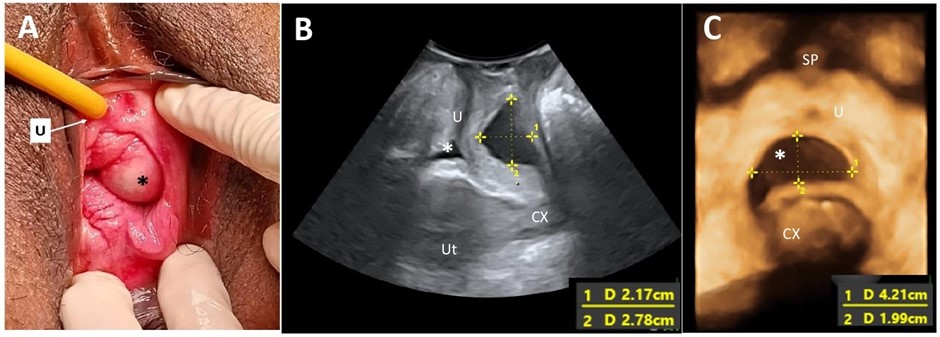

Cystic lesions of the vagina are relatively rare, and their prevalence may be underestimated due to underreporting of vaginal cysts. These lesions are classified according to their histological characteristics. A Gartner’s duct cyst, a benign variant, originates from the Gartner’s duct, which is a remnant of the mesonephric duct (Wolffian duct) in females. While these cysts are predominantly asymptomatic, they may be identified in patients presenting with pelvic organ prolapse. A comprehensive medical history, meticulous physical examination, and accurate imaging are essential for ensuring appropriate management of affected individuals.